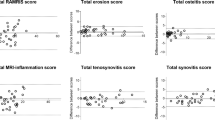

Drawn ROIs in bone marrow edema-like signal had a mean diameter of 4.8 ± 1.5 mm, range 4 to 9 mm. Drawn ROIs in healthy tissue had a mean diameter of 8.5 ± 2.3 mm, range 5 to 15 mm. Results of average signal intensity measurements in bone marrow edema-like signal are given in Fig. 2. Obtained signal intensity values were highly variable. For measurements in bone marrow edema-like signal on STIR images, the correlation coefficient before and after contrast agent administration was 0.79 (95% CI 0.60 to 0.89) for reader 1 and 0.76 (95% CI 0.55 to 0.88) for reader 2. In healthy tissue, the correlation coefficient before and after contrast agent administration was 0.95 (95% CI 0.91 to 0.98) for reader 1 and 0.94 (95% CI 0.88 to 0.97) for reader 2.

Correlation of average signal intensity of A bone marrow edema-like signal and B healthy tissue on precontrast STIR and postcontrast STIR images. Measured average signal intensity (SI) on precontrast STIR and postcontrast STIR images in A bone marrow edema-like signal and B healthy tissue for both readers. Reader 1 is represented by black dots; reader 2 is represented by white circles. The diagonal line indicates the 1:1 relationship expected if there is no change in signal intensity after contrast agent administration

The distributions of relative signal intensity changes after intravenous contrast for bone marrow edema-like signal and healthy tissue are given in Fig. 3.

Relative signal change as percentage values (%) between precontrast STIR and postcontrast STIR images. Boxplots of relative signal change (% of SI on precontrast STIR images) between measured signal intensity (SI) on precontrast STIR images compared to postcontrast STIR for bone marrow edema-like signal and healthy tissue for both readers. Horizontal line indicates median; lower and upper edge of box indicates first and third quartile. Whiskers represent minimum and maximum, outliers excluded. Outliers (> 1.5 IQR) are indicated by circles. Relative signal change (precontrast to postcontrast) differed significantly between bone marrow edema-like signal and healthy tissue for both readers (p < 0.001, Wilcoxon signed-rank test)

For reader 1, median relative signal change on postcontrast STIR compared to precontrast STIR images for bone marrow edema-like signal measurements was -35% (IQR 24, 1st quartile -52%, 3rd quartile -28%), whereas median relative signal change in healthy tissue was -2% (IQR 15, 1st quartile -10%, 3rd quartile 5%).

For reader 2, median relative signal change on postcontrast STIR compared to precontrast STIR images for bone marrow edema-like signal measurements was -34% (IQR 21, 1st quartile -40%, 3rd quartile -20%), whereas median relative signal change in healthy tissue was 0% (IQR: 17, 1st quartile -12%, 3rd quartile 6%).

For both readers, relative signal changes on postcontrast STIR compared to precontrast STIR images in bone marrow edema-like signal differed significantly from those in healthy tissue (Wilcoxon signed-rank test, p < 0.001).